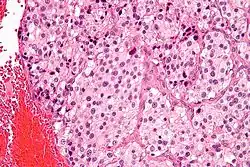

| Micrograph of a carotid body tumor (a type of paraganglioma) | |

On microscopic inspection, the tumor cells are readily recognized. Individual tumor cells are polygonal to oval and are arranged in distinctive cell balls, called Zellballen.[9] These cell balls are separated by fibrovascular stroma and surrounded by sustentacular cells.

By light microscopy, the differential diagnosis includes related neuroendocrine tumors, such as carcinoid tumor, neuroendocrine carcinoma, and medullary carcinoma of the thyroid.

With immunohistochemistry, the chief cells located in the cell balls are positive for chromogranin, synaptophysin, neuron specific enolase, serotonin, neurofilament and Neural cell adhesion molecule; they are S-100 protein negative. The sustentacular cells are S-100 positive and focally positive for glial fibrillary acidic protein. By histochemistry, the paraganglioma cells are argyrophilic, periodic acid Schiff negative, mucicarmine negative, and argentaffin negative.

Micrograph of a carotid body tumor -